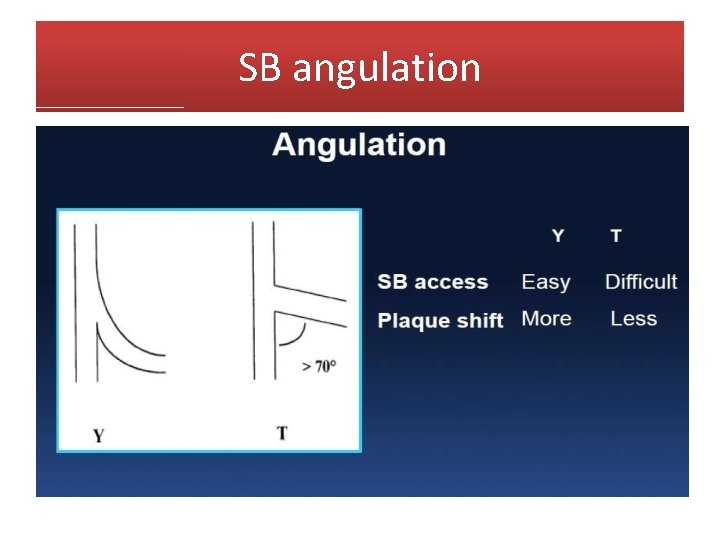

SB angulation